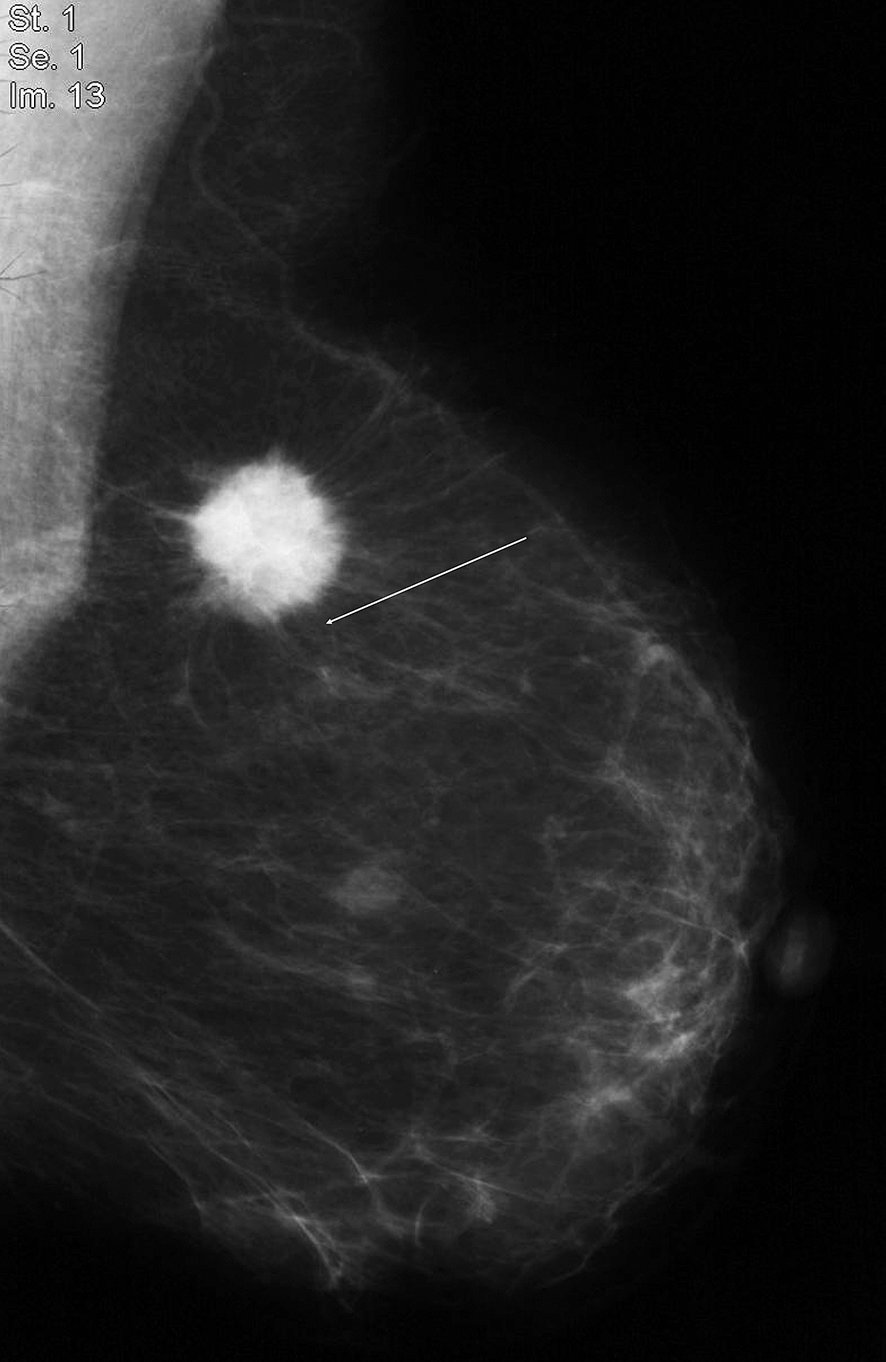

Figure 20.7 Masse dense à contours irréguliers, avec spicules courts partant du bord de la masse.